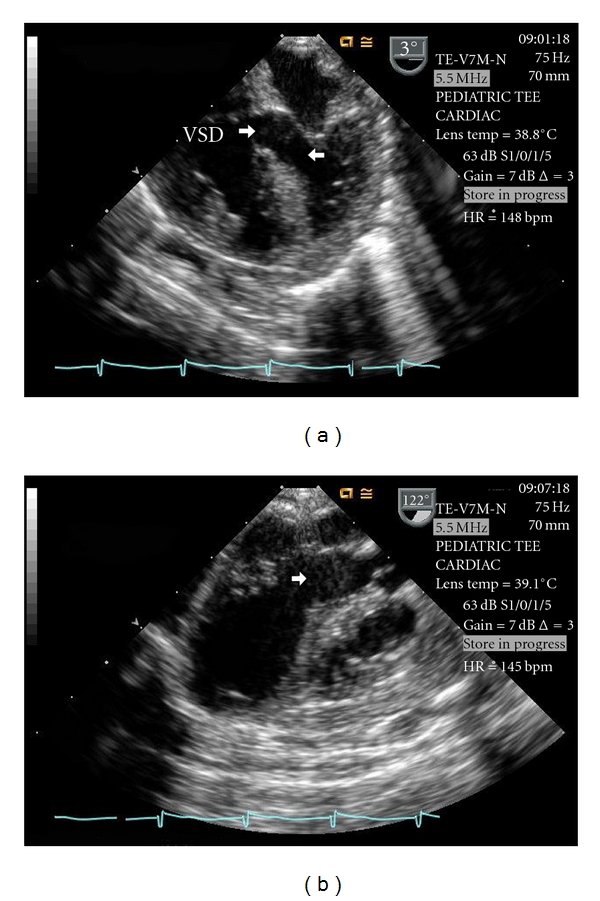

Dissecting ventricular septal hematoma (DVSH) rarely occurs after repair of a ventricular septal defect (VSD) but can lead to serious complications such as septal rupture, myocardial rupture, cardiogenic shock, heart block, outflow obstruction, cardiac tamponade, abscess transformation, and death. This paper describes the diagnosis and management of acute, severe, left ventricular outflow tract obstruction caused by the development of a DVSH after VSD repair.